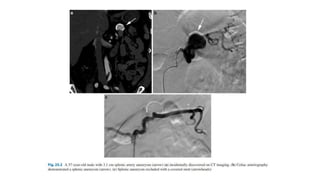

Visceral Aneurysms

Visceral Artery True Aneurysms (VATAs)-:

• VATAs occur due to vessel wall degeneration with a defect in the

arterial media, loss of the elastic fibers, and decreased smooth

muscle volume.

• Atherosclerosis, fibromuscular dysplasia, congenital syndromes, and

collagen disorders are all precursors to VAAs.

• The most common VATAs is the Splenic artery followed by the

Pancreaticoduodenal arcade.

Visceral Artery Pseudoaneurysm (VAPA

• Visceral artery pseudoaneurysms occur most commonly due to

chronic inflammation caused by conditions such as pancreatitis,

infection or vasculitis, blunt, or penetrating trauma or iatrogenic

etiologies such as surgery or percutaneous procedures.

• The most common site for VAPAs is the Hepatic artery.

Visceral Aneurysms Visceral ArteryTrue Aneurysms (VATAs)-: • VATAs occur due to vessel wall degeneration with a defect in the arterial media, loss of the elastic fibers, and decreased smooth muscle volume. • Atherosclerosis, fibromuscular dysplasia, congenital syndromes, and collagen disorders are all precursors to VAAs. • The most common VATAs is the Splenic artery followed by the Pancreaticoduodenal arcade.

• 70.

Visceral Artery Pseudoaneurysm(VAPA • Visceral artery pseudoaneurysms occur most commonly due to chronic inflammation caused by conditions such as pancreatitis, infection or vasculitis, blunt, or penetrating trauma or iatrogenic etiologies such as surgery or percutaneous procedures. • The most common site for VAPAs is the Hepatic artery.